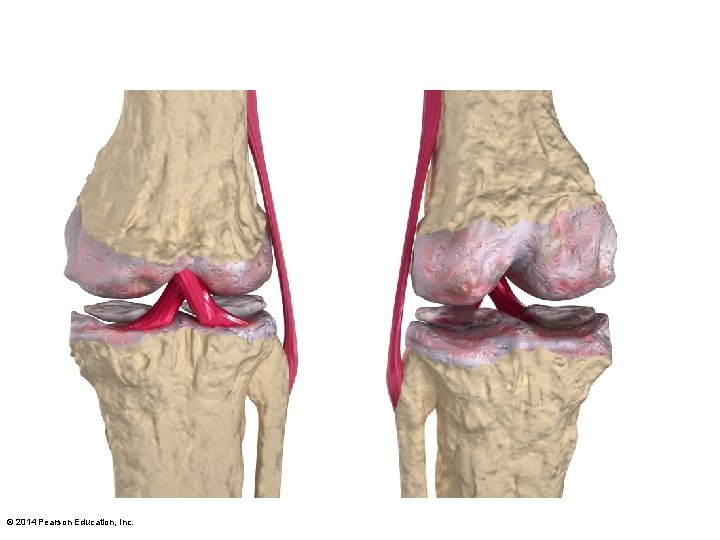

Figure 8. 8 e–f The knee joint. Fibular collateral ligament Lateral condyle of femur Lateral meniscus Tibia Posterior cruciate ligament Medial condyle Tibial collateral ligament Anterior cruciate ligament Medial meniscus Medial femoral condyle Anterior cruciate ligament Medial meniscus on medial tibial condyle Patellar ligament Fibula Patella Quadriceps tendon Anterior view of flexed knee, showing the cruciate ligaments (articular capsule removed, and quadriceps tendon cut and reflected distally) © 2014 Pearson Education, Inc. Patella Photograph of an opened knee joint; view similar to (e)

Figure 8. 8 b The knee joint. Anterior cruciate ligament Articular cartilage on medial tibial condyle Medial meniscus Posterior cruciate ligament Anterior Articular cartilage on lateral tibial condyle Lateral meniscus Superior view of the right tibia in the knee joint, showing the menisci and cruciate ligaments © 2014 Pearson Education, Inc.

Figure 8. 9 A common knee injury. Lateral Hockey puck Medial Patella (outline) Tibial collateral ligament (torn) Medial meniscus (torn) Anterior cruciate ligament (torn) © 2014 Pearson Education, Inc.